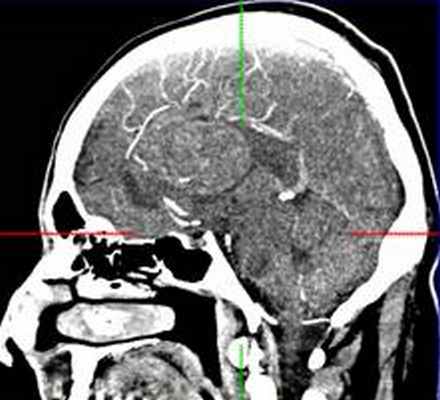

МРТ головного мозга (14.04.15): в правой лобной доле объемное кистозно-солидное образование неправильной округлой формы, с четкими неровными контурами, распространяющееся в левую лобную долю, размерами 5,6х6х5,5 см. Срединные структуры на уровне прозрачной перегородки смещены влево на 18 мм.

КТ головного мозга (06.07.15): гигантская двухсторонняя опухоль нижнего края фалькса, задне-лобно-теменной области. Стадия декомпенсации. Перитуморальный отек. Опухоль достигает 3 желудочка.